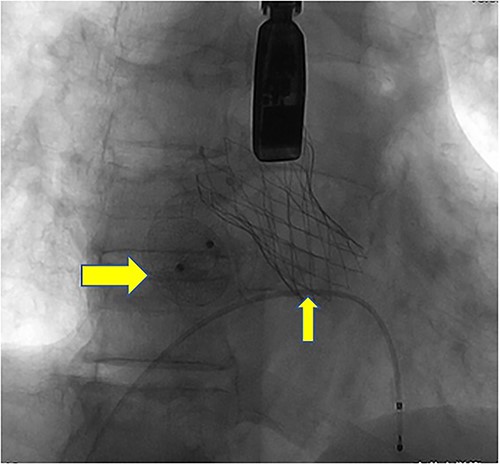

Postoperatively, imaging studies, including TEE and digital subtraction angiography (DSA), confirmed normalization of aortic valve flow velocity and pressure gradients, with the absence of aortic regurgitation (Fig. 7). Atrial shunting disappeared, and there was no involvement of the mitral or tricuspid valves. Both the self-expanding valve prosthesis and the closure device were stably positioned, and the surgical outcome was deemed successful (Fig. 8). One month after surgery, the patient’s symptoms of chest tightness and shortness of breath had resolved.

Postoperative DSA: Digital subtraction angiography confirms the proper positioning of the aortic self-expanding valve (thin arrow) and occluder (thick arrow).